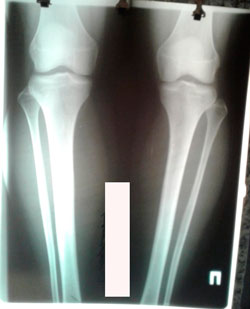

Исходник 18 лет.

Дата операции - 18.09.2020